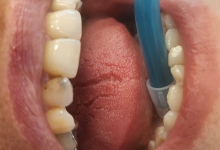

Clinica LUY ESTHETIC ART defineste parodontoza ca fiind rezultatul direct al placii dentare, care se depune pe suprafata dintilor, dar si in apropiere de marginea gingivala. Aceasta boala duce la pierderea dintilor, chiar daca ei sunt aparent sanatosi si nu prezinta carii. Edentatiile, afecteaza vorbirea, aspectul, dar si capacitatea de a mesteca.

Boala parodontala are un caracter progresiv. Pentru cazurile mai grave, recomandam tratamentul parodontal chirurgical rezectiv sau regenerativ.

O igiena bucala necorespunzatoare, fumatul, placa bacteriana si alte boli generale, permit bacteriilor sa se dezvolte in cavitatea bucala.